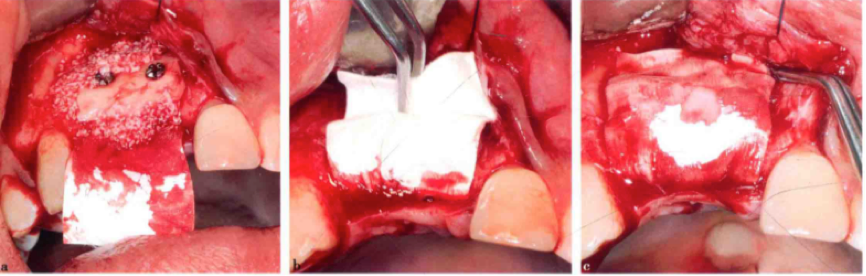

骨块修整

去皮质化

钛钉固定骨块

固定骨块后充填骨粉覆盖胶原膜